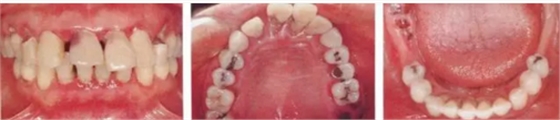

病例7

在正畸治療結(jié)束后仍然存在open contact的病例

▲圖15-1,2

在正畸??漆t(yī)生處接受了正畸治療,雖然上頜正畸治療已經(jīng)完成,但由于磨牙區(qū)的邊緣嵴不整齊而導(dǎo)致牙體之間存在空隙。要想在這個狀態(tài)下護(hù)理牙周組織以及咬合狀況是非常困難的。由此可見,在治療時,正畸??漆t(yī)生與全科口腔醫(yī)生保持目標(biāo)一致是非常重要的。